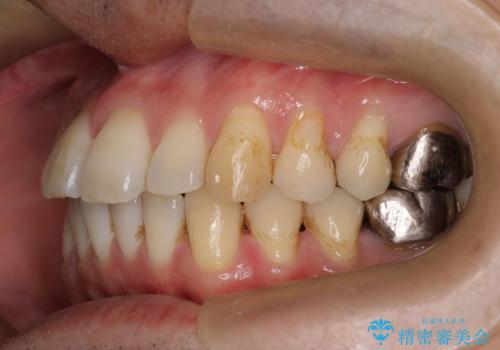

- 前歯の出ているのが気になる、下唇を噛んで痛いとのことで来院された患者様です。マウスピース矯正をご希望でした。

奥歯の噛み合わせはしっかりしていましたので、奥歯の動きは最小限にし、前歯の並びに集中した治療計画+インビザラインのシミュレーションを作成しました。

奥歯の噛み合わせは整っていたため、前歯の並びを美しく修正することに専念できました。マウスピース矯正による治療で短期間で改善しました。